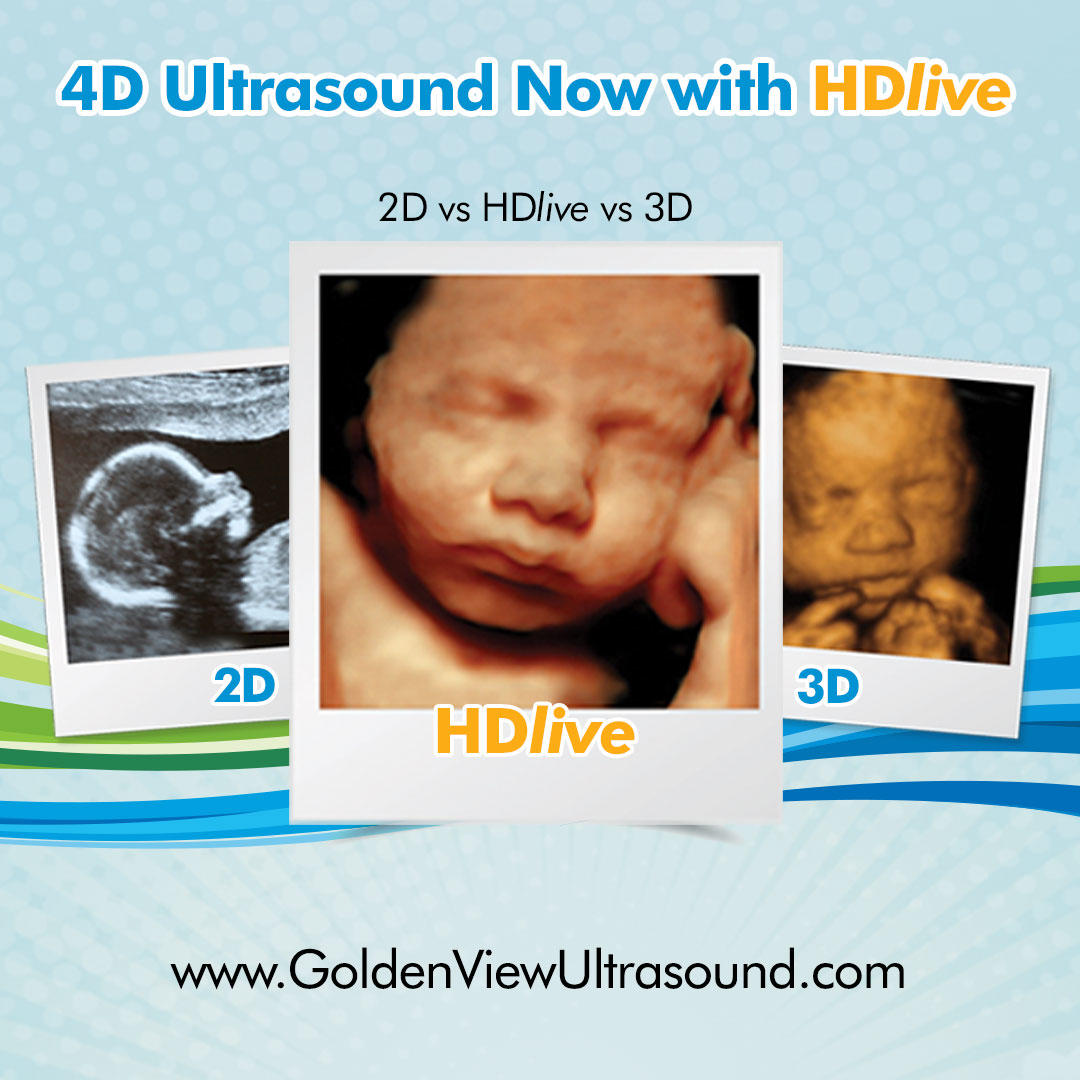

San Antonio’s Premiere 3d Ultrasound, 4d Ultrasound & HDLive (5D) Ultrasound facility specializes in prenatal ultrasound. GoldenView Ultrasound offers Ultrasound services for Expectant mothers in San Antonio. New Braunfels, Boerne, Schertz, Lackland Airforce Base, Randolf Airforce Base and other surrounding San Antonio area communities that want to capture the 4D Ultrasound on video and with 3D photos of their baby in the womb. Early Gender Reveal Ultrasounds are offered starting at 14 weeks gestation. Find out if you are having a boy or a girl and get beautiful images of your baby in the womb. Also offering Pregnancy Verificaiton / Confirmaiton starting at 6+ weeks. Digital photos on CD-rom, USB or sent directly to you via our own app. We utilize the latest and most advanced 3d/4d Ultrasound machine with HDLive. HDLive ultrasound, sometimes referred to as "5D" Ultrasound provides a high definition view of the baby in the womb with unsurpassed clarity. GoldenView Ultrasound is the first 3d/4d prenatal ultrasound facility in the San Antonio area to offer HDLive Ultrasound. Our spa like facility is spacious and allows family and friends to join the ultrasound appointment. We do not limit the number of guests that can attend the ultrasound and children of all ages are always welcome. The 3d/4d/HD Ultrasound is displayed on a large screen TV for easy viewing. Family and friends that are far away can always view via Live Internet streaming of your ultrasound and clients can also purchase a recorded session that includes a digital download of their baby's ultrasound. Live Internet streaming is Free to military Dads that are deployed plus we offer a military discount on all 2d, 3d/4d and HD ultrasound services. You can also get a recording of your baby's heartbeat inside one of our adorable stuffed animals. Our Heartbeat Huggables with the fetal heartbeat recording inside make a great gift for siblings to be or as a special keepsake for the parents or grandparents. Choose from a Heartbeat Teddy bear or a large variety of other adorable stuffed animal.

We have imaged over 80,000 babies with 3d/4d ultrasound since 2005 and have been offering HDLive Ultrasound since 2015. We have registered ultrasound techs on staff and a Board Certified Physician acting as our Medical Director. GoldenView Ultrasound offers experience from 12+ years in business combined with the latest in ultrasound equipment to give expectant parents the best and most memorable experience possible. Customer loyalty discounts are available to anyone that visited us during a previous or current pregnancy in addition to military discounts and student discounts.